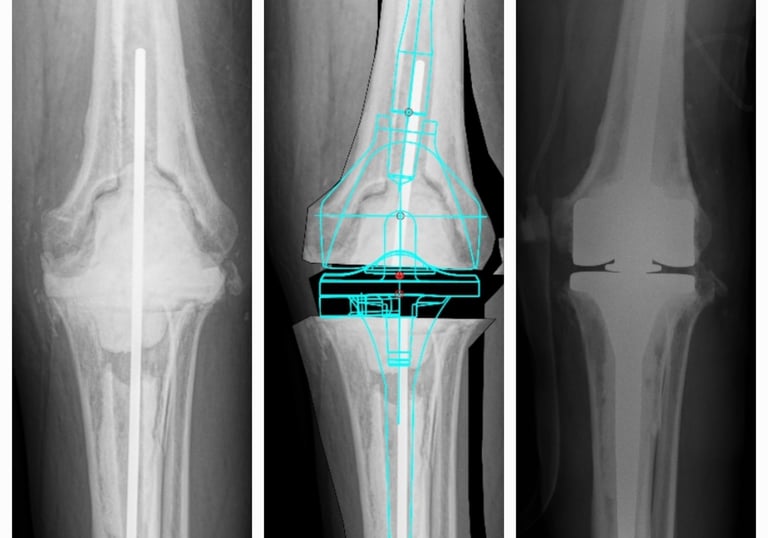

Cirugía de revisión de rodilla

Cirugía en la que se reemplaza la articulación dañada por una prótesis nueva. Se realiza en casos de desgaste severo, artrosis o lesiones que provocan dolor intenso y limitan la movilidad. El objetivo es devolver la capacidad de caminar, realizar actividades cotidianas sin dolor y mejorar la calidad de vida.

Prótesis de cadera y rodilla